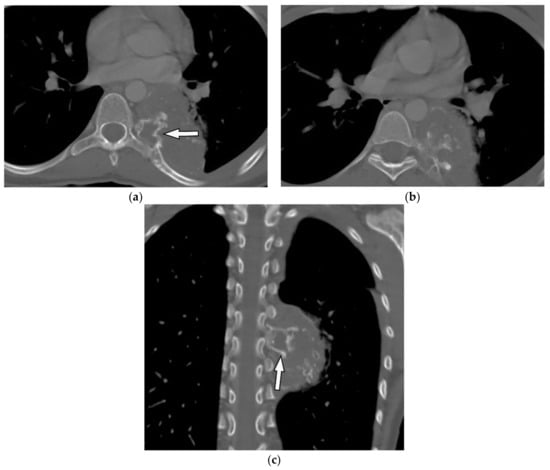

8.2. Tuberculosis Spondylodiskitis

Tuberculosis spondylodiskitis has a more gradual and chronic clinical course, which leads to multi-level involvement and paravertebral cold abscess formation with well-circumscribed thin wall. Subligamentous spread of infection to adjacent vertebral levels, relative preservation of intervertebral disk, and kyphotic angulation (gibbous deformity) are other imaging findings. CT scan is more sensitive in delineating calcification within paravertebral cold abscess, end plate erosion, and bony fragment visualization (Figure 13) [39,42].

Figure 13.

A 65-year-old man with fever, weight loss, and night sweeting. The non-contrast-enhanced CT (bone window) in axial plane (a) shows paraspinal soft tissue mass with erosion of right lateral aspect of adjacent vertebral body. Sagittal T2W image of another patient with the same pathology (b) shows hypersignal intensity within T8-T9 vertebral bodies with also intervertebral disc destruction and narrowing of spinal canal pushing the spinal cord posteriorly. Axial T1WFS + C (c) identified the enhancing paraspinal mass with peripheral rim enhancement (arrow) in its left posteromedial side, which is suggestive of abscess formation. Culture of aspirated pus under guide of CT was compatible with tuberculosis infection.